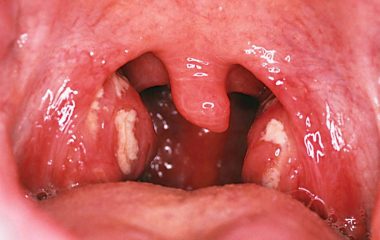

Катаральная ангина является одной из самых распространенных форм тонзиллита. Лечение проводится различными препаратами.